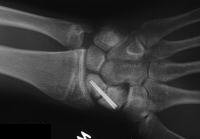

Clinical Example: Revision scaphoid nonunion with hardware removal, bone graft and two Herbert screws

This 19 year old had been treated elsewhere with an accutrac screw for a displaced scaphoid fracture. He was noncompliant with immobilization after surgery, and developed a painful nonunion.

The nonunion was reconstructed by removing the hardware, iliac bone graft and two Herbert screws placed through new paths. Cancellous bone was packed into the old screw hole.